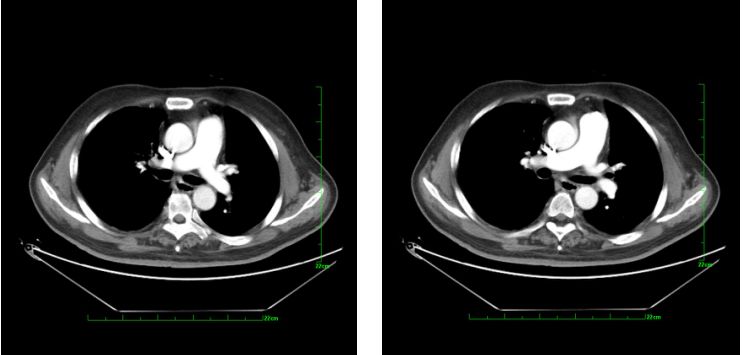

修正诊断:急性肺栓塞。给予阿替普酶50 mg静脉溶栓,之后依诺肝素80 mg ih q12h。复查血气分析:pH 7.5(↑),PCO225.2 mmHg(↓),PO264.9 mmHg(↓),SO294.5%(↓),PO2(A-a)50.0 mmHg(↑)。患者仍觉活动后胸闷,于2014年11月5日行肺动脉造影、肺动脉血栓导管碎解及血栓抽吸,术中测肺动脉压为60/27 mmHg,手推造影剂,可见肺动脉近段多处充盈缺损,先后送入7F长鞘,反复捣碎、抽吸,抽出大量新鲜血栓。再次造影后见肺动脉充盈缺损明显减轻(图2)(图3),测肺动脉压为47/8 mmHg。其后给予阿替普酶50 mg+生理盐水50 ml,2小时静脉泵入。泵入完毕后给予依诺肝素80 mg ih q12h,加用华法林抗凝。术后1周复查肺动脉CTPA示左、右肺动脉主干血栓消失,远端分支少许血栓(图4)。病情好转出院。

图4.术后1周复查肺动脉CTPA左、右肺动脉主干血栓消失,远端分支少许血栓